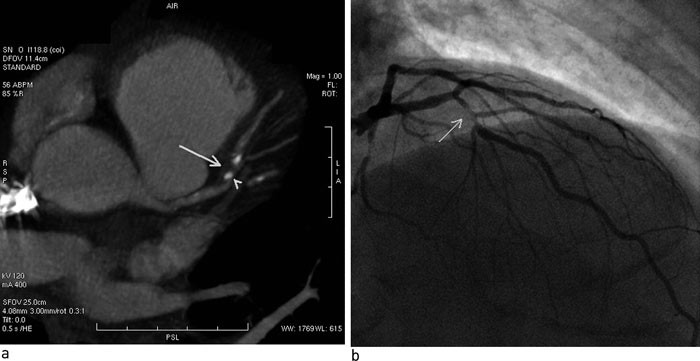

Koronarkara er småkalibra og beveger seg med hjartet. CT-maskinar har tidlegare ikkje hatt tilstrekkeleg romleg og tidsmessig oppløysing til å framstille desse årene godt nok. Ved multidetektor-CT har spiral-CT-maskinane fått fleire parallelle detektorrader, frå fire i 1998 til heile 320 frå 2007. Dette gjer det mogleg å samle biletdata frå mange parallelle kroppsskiver samtidig (fig 1). Eksempel på ferdige bilete er gitt i figur 2 og figur 3.